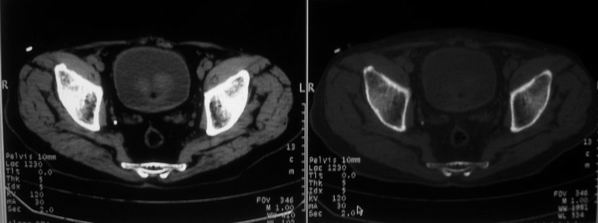

男,85岁,排尿困难。骶椎有问题吗?

前列腺明显增大,突入膀胱,各叶比例协调,密度均匀,精囊腺及精囊角正常;考虑良性增大。

骶骨没有看到明显异常。

1)前列腺明显增大,突入膀胱,各叶比例协调,密度均匀,精囊腺及精囊角正常;考虑前列腺增生症并阻塞性膀胱炎。2)骶椎右侧类似囊状骨质密度减低区,边缘骨质硬化,其内为软组织密度影填塞,相邻之骶椎椎管受压变形;考虑为骶椎右侧囊肿或神经纤维瘤。

建议:行mri检查。